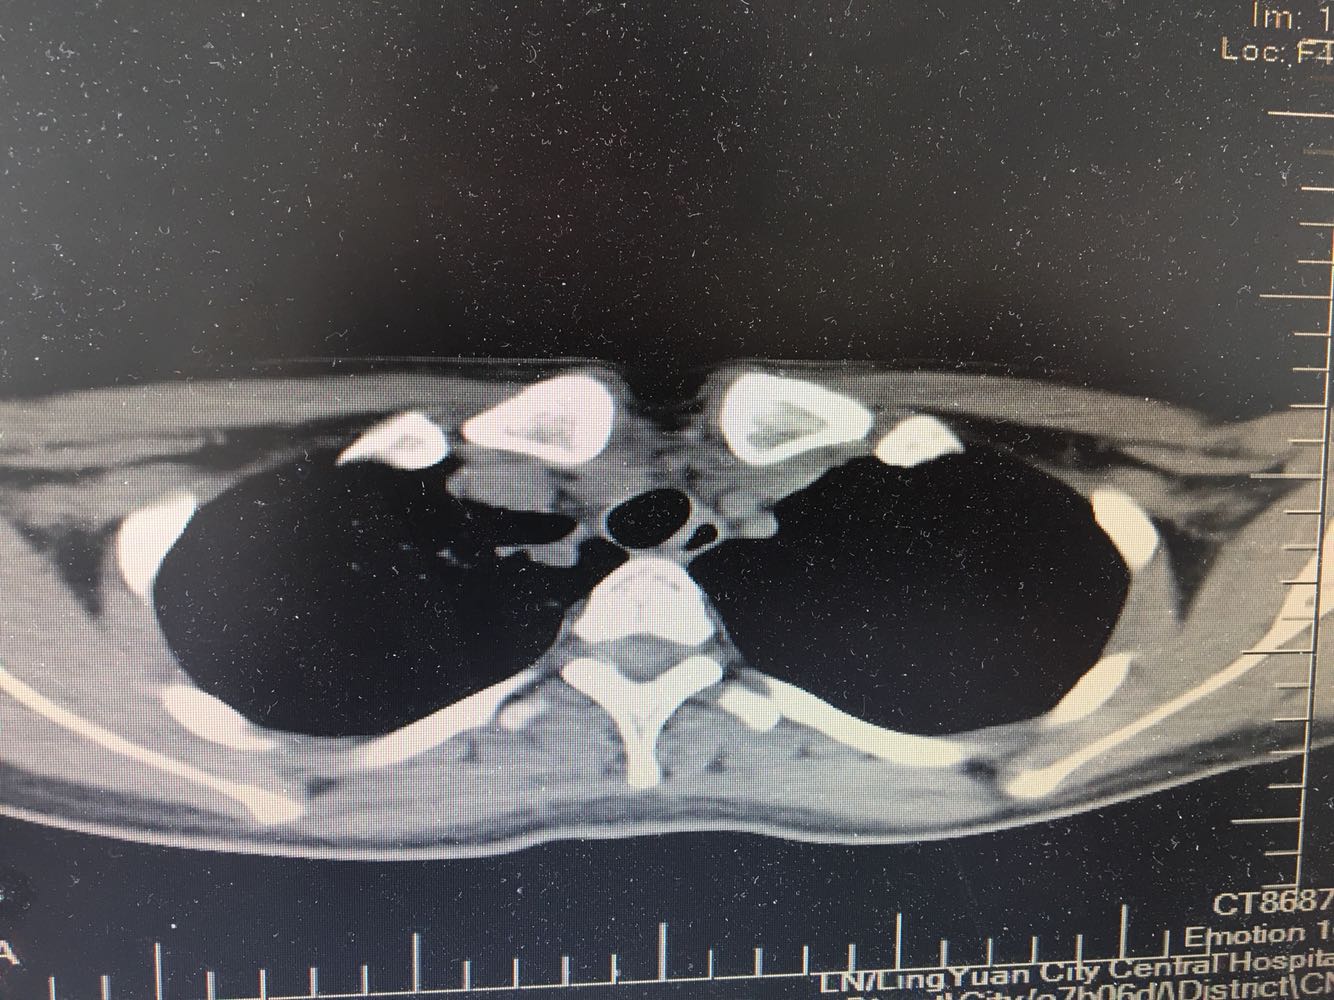

女,26岁,咳嗽1周,咳痰不畅,咽喉痒,口服阿莫西林无好转,昨日发热,体温38.5摄氏度,于门诊查肺CT后以肺炎收入院,病来无盗汗,无咳血,无消瘦及乏力,无头痛,无肢体酸痛,饮食睡眠可,二便正常

神清言明,咽部无充血,扁桃体不大,双肺呼吸音清,无罗音,服软无压痛。

支原体抗体1:160,结核抗体弱阳性。支原体肺炎个别可见上叶病变,该患无结核中毒症状,考虑支原体肺炎可能性大,但肺尖为结核好发部位,需要抗炎治疗后复查观察疗效。